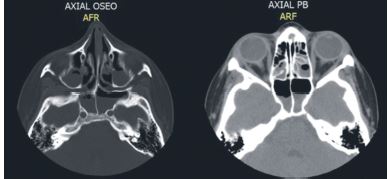

La tomografía axial (TAC) máxilo facial muestra velamiento de todas las cavidades perinasales con niveles hidro-aéreos de senos maxilares y senos esfenoidal (Figuras 2, 3 y 4), confirmando el diagnóstico imagenológico de PA.

Cuando el origen de la PA es dental, es necesario el control de la evolución del caso, mediante radiografías periapicales y TAC12; en este caso fue imprescindible la información dada por las imágenes del TAC para observar el velamiento de las cavidades de la región Máxilo facial y su adecuado diagnóstico.